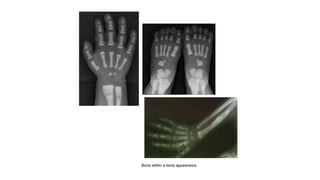

Osteopathia striata:

⮚ It is a benign condition with a X-linked dominant

inheritance.

⮚ It is more commonly seen in females

⮚ It is characterised by bilateral symmetric involvement

of long bones, pelvis and scapulae in the form of

multiple vertical radio opaque lines in the metaphysis

extending into the diaphysis (celery stalk metaphysis).

⮚ In the pelvis, this gives a sunburst effect.

Vertical striations around the knee in

osteopathia striata

AP radiograph shows linear striations throughout the osseous

pelvic structures. Note the fan-shaped appearance of the

striations in the iliac crests.